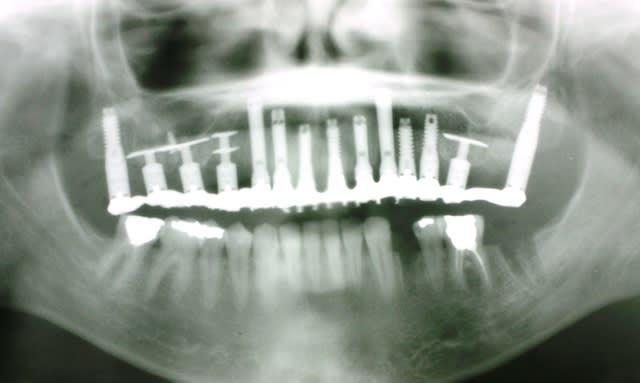

Patient vu en début d'année, parodontite en phase terminale, "monsieur je pense qu'il faudrait vous enlever quelques dents" (voir pano). Lui pas trop pressé apparemment.

Oui bien sûr placé sous 48 h

Les piliers seront retirés sur les molaires par la suite

Pour me faire un idée...

c'est combien le devis de cette arcade d'implants,

au total. Merci